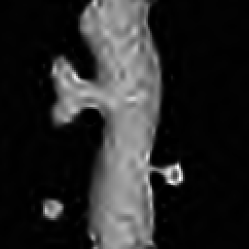

In Fig.1(a), a phantom of a neuron with a mushroom-shaped spine is depicted. The maximum intensity is 30. Its blurred and blurred+noisy versions are in (b) and (c). With this neuron, and for NaiveGauss, AnsGauss and our approach, the dictionary ΦΦ\Phi contained the wavelet orthogonal basis. The deconvolution results are shown in Fig.1(d)-(h). As expected the worst results are for the AnsGauss version, as it does not take care of the non-linearity of the Anscombe VST. RL-TV shows rather good results but the background is full of artifacts. Our approach provides a visually pleasant deconvolution result on this example. It efficiently restores the spine, although the background is not fully cleaned. RL-MRS also exhibits good deconvolution results. Qualitative visual results are confirmed by quantitative measures of the quality of deconvolution, where we used both the 1subscript1\ell_{1}-error (adapted to Poisson noise), and the traditional MSE criteria. The 1subscript1\ell_{1}-errors for this image are shown by Tab. 1 (similar results were obtained for the MSE). In general, our approach performs well. It is competitive compared to RL-MRS which is designed to directly handle Poisson noise. At low intensity regimes, our approach and RL-MRS are the two algorithms that give the best results. At high intensity, RL-TV performs very well, although RL-MRS, NaiveGauss and our approach are very close to it. NaiveGauss performs poorly at low intensity as it does not correspond to a degradation model with Poisson noise. AnsGauss gives the worst results probably because it does not handle the non-linearity of the degradation model (2) after the VST. To assess the computational burden of the compared algorithms, Tab. 2 summarizes the execution times with an Intel PC Core 2 Duo 2GHz, 2Gb RAM. Except RL-MRS which is written in C++, all other algorithms were implemented in MATLAB.

Fig. 1: Deconvolution of a simulated neuron (Intensity \leqslant 30). (a) Original, (b) Blurred, (c) Blurred&noisy, (d) RL-TV, (e) NaiveGauss, (f) AnsGauss, (g) RL-MRS, (h) Our Algorithm.